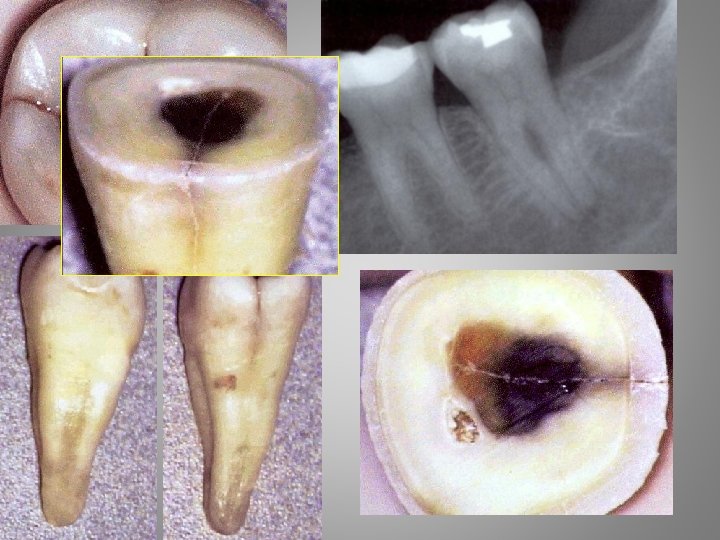

Types of orofacial pain Odontalgia : - Exposed dentin - Caries - Pulpitis - Apical periodontitis - Craced tooth sy. - Occlusal trauma - Periodontal abscessacute necrotising gingivitis - Periodontitis

Caries Pain - food penetration - esthetic disorder - bad smell and taste - gingivitis Big lesion - X-ray, fiberoptic - change of tha approximal contour